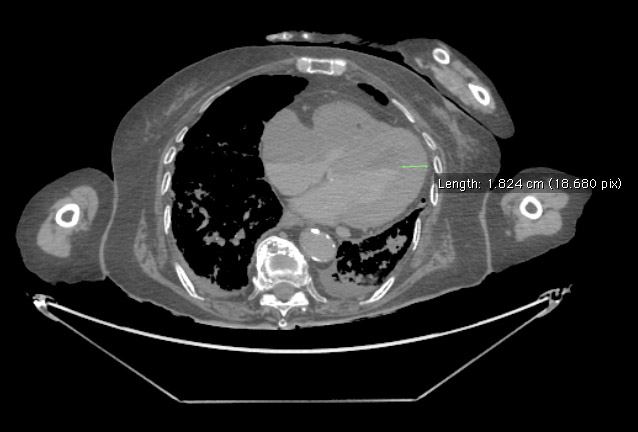

Another measurement was taken of the left ventricular wall thickness, which is normally between 0.6-1.1 cm. As you can in the screenshot below, we measured cadaver 33522's left ventricuar wall thickness to be 1.82 cm, indicating that left ventricular hypertrophy is a component of this patient's cardiomegaly.

Image obtained from the Creative Commons database.